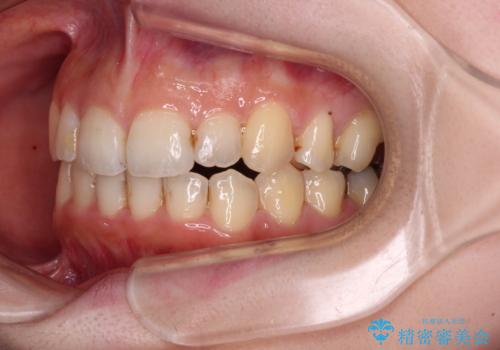

- 顕著な八重歯など、上下前歯のデコボコとスペースを気にして来院された患者様です。

八重歯改善には第一小臼歯の抜歯が必要であり、移動量が多いことから補助装置により八重歯を引き込むこととしました。

インビザラインでの治療をご希望であったので、インビザラインにて行うこととしましたが、右側前歯の改善にはワイヤー矯正が必要となる可能性があることをお伝えした上で治療を開始しました。

補助装置だけでなく、部分的にワイヤー矯正も使用しましたが、上下のスペースは改善しきれず、側切歯(前から2番目の歯)や顕著な八重歯は、インビザラインで治療するには限界があることがよく分かりました。

より良い仕上がりを希望される場合には、ワイヤー装置による矯正治療がお勧めとなります。